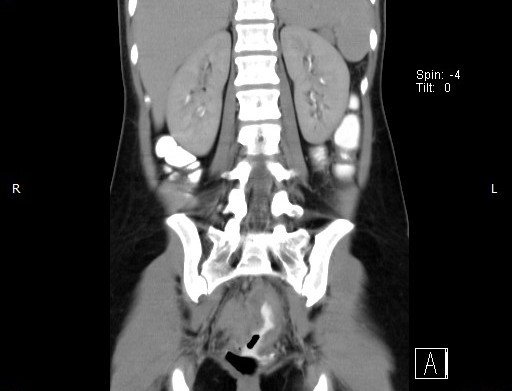

Abdominal CT images

CT finding : Circumferential rectal wall thickening-> Tissue diagnosis -> Rectal cancer

CT finding correlated with plain abdominal radiograph